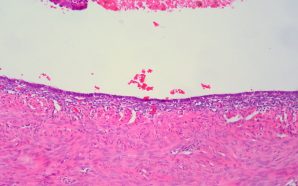

- “Endo what?”, she said. This is a common response of those who have never encountered this disease. Pronounced en-do-me-tri-osis, it is one of the most complex...